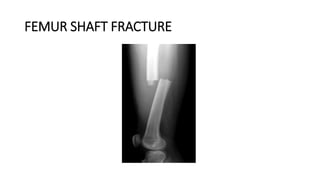

FEMUR SHAFT FRACTURE

DEFINITION

• Femur (Thighbone) is the longest and strongest bone in the body.

Because the femur is so strong, it usually takes a lot of force to break

it. Motor vehicle collisions, for example, are the number one cause of

femur fractures.

• The long, straight part of the femur is called the femoral shaft. When

there is a break anywhere along this length of bone, it is called a

femoral shaft fracture. This type of broken leg almost always requires

surgery to heal.

(Left) An oblique fracture has an angled line

across the shaft. (Right) A comminuted fracture

is broken into three or more pieces.